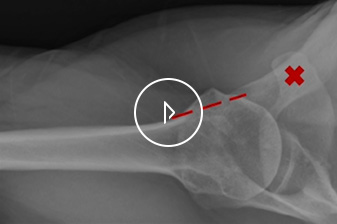

Musculoskeletal ultrasound is an injury assessment technique that uses sound waves to create images of painful or injured soft tissues in the extremities.